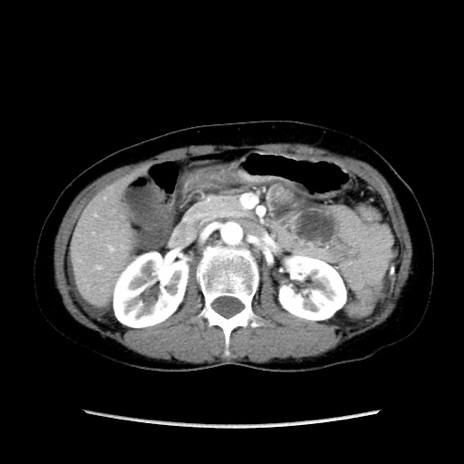

冠状断像